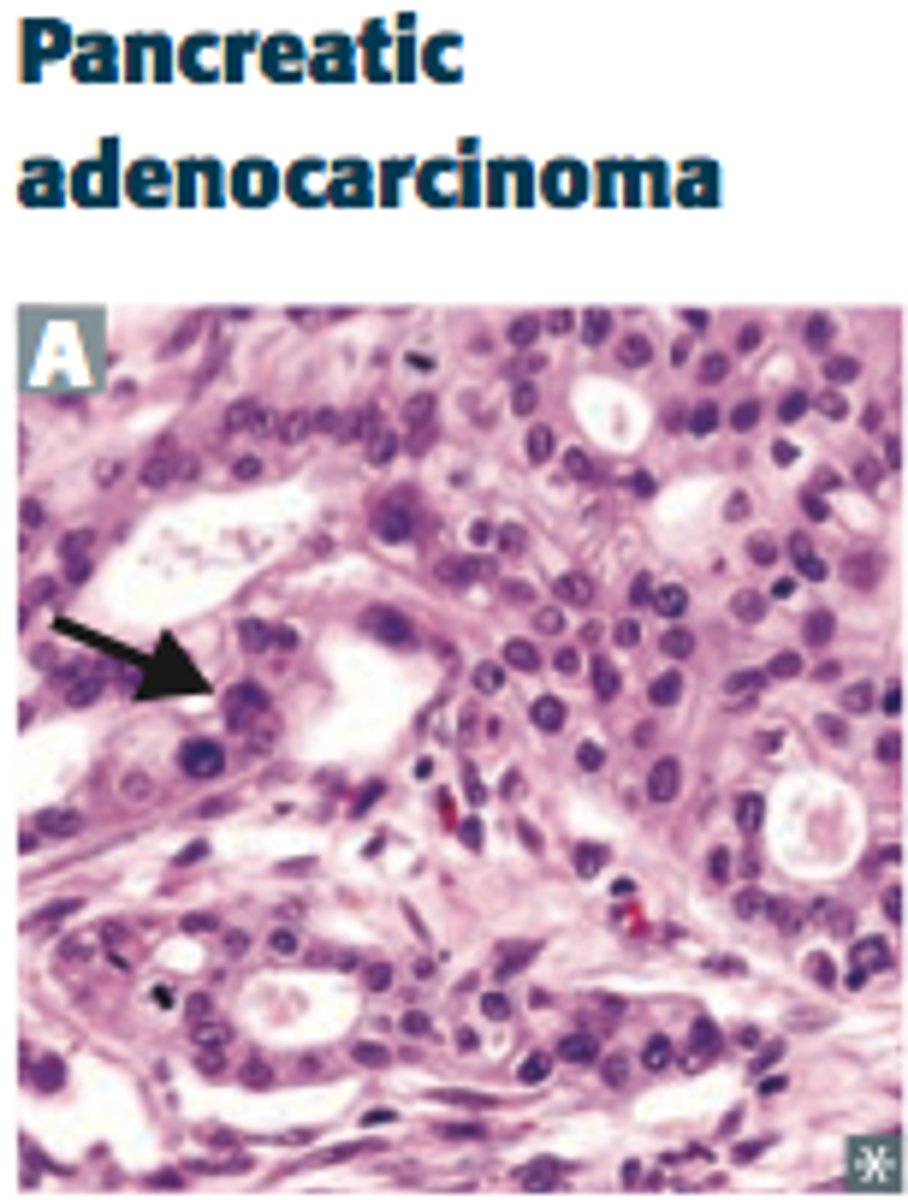

Painless jaundice

Cancer of the pancreatic head obstructing the bile duct